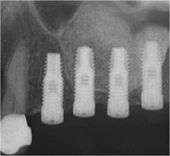

In some cases the dental implant is also inserted during the same sinus lift procedure.

As an alternative, sinus augmentation can be performed by a less invasive osteotome technique. This technique is normally performed when the sinus floor needs to be lifted less than 4 mm. The osteotome technique is performed by flapping back gum tissue and making a socket in the bone within 1–2 mm short of the sinus membrane. The floor of the sinus is then lifted by tapping the sinus floor with the use of osteotomes. The amount of augmentation achieved with the osteotome technique is usually less than what can be achieved with the lateral window technique. A dental implant is normally placed in the socket formed at the time of the sinus lift procedure and left to integrate with bone. Bone integration normally lasts 4 to 8 months. The goal of this procedure is to stimulate bone growth and form a thicker sinus floor, in order to support dental implants for teeth replacement.

Once the initial lift is complete, the surgeon drills a socket in the bone that is sized to the new implant. Bone graft material is added again with pressure to further lift the sinus until it is raised to the proper height for implant placement. The surgeon then places the dental implant into the bone socket and sutures the gums back into place.